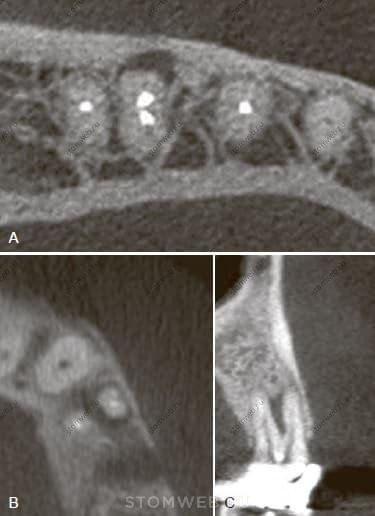

Вертикальные переломы корня часто возникают в зубах с овальным поперечным сечением корня, когда корень шире в язычно-щечном направлении, чем проксимально. Это верхние и нижние премоляры, медиальные корни нижних моляров и нижние резцы (Рис. 21-25, А и В). Такая форма может быть наглядно представлена на поперечных срезах КЛКТ (см. рис. 21-25 А и В). Перелом в этих зубах обычно начинается в щечно-язычной плоскости , а именно, в области наибольшей выпуклости корня (см. рис. 21-25, А и В). Данное заключение на основе изучения большого количества клинических случаев подтверждено также методом анализа конечных элементов. Этот метод четко продемонстрировал концентрирование напряжений на внутренней поверхности дентина в наиболее выступающих частях (то есть со щечной и язычной сторон овального корня) (рис. 21-26).

РИС 21-25 Анатомические предрасполагающие факторы. А) Поперечный срез КЛКТ верхней челюсти, на котором видна овальная форма поперечного сечения каналов клыка и второго премоляра. В) Поперечный срез нижней челюсти, демонстрирующий овальную форму каналов резцов, клыков, премоляров и дистальных корней моляров. Овальное строение в сочетании с эндодонтическим лечением связывают с более высокой вероятностью образования вертикальных переломов корня. С, D) Вогнутость с дистальной стороны медиальных корней нижних моляров также является зоной риска, когда при избыточной инструментальной обработке в сочетании с выпрямлением канала происходит истончение дентинной стенки с концентрацией напряжения в этой области. E, F) Вогнутость небной поверхности щечного корня первого верхнего премоляра (Е - срезы; F - поперечный срез КЛКТ исследования). Такие углубления также могут стать потенциальной зоной риска. Ни одна из вогнутых поверхностей на изображениях С, D, E, F не будет видна на прицельном снимке. Необходимо отметить, что КЛКТ исследование не следует проводить по умолчанию при плановых осмотрах, а только в соответствии с показаниями, обозначенными компетентными органами (Американская Ассоциая Эндодонтистов, Американская академия оральной и Челюстно-лицевой радиологии)

РИС. 21-26 Анализ конечных элементов распределения напряжений в овальном корне. Обратите внимание на концентрацию напряжения на внутренней поверхности наиболее выпуклой части сохраненного дентина. Красным и оранжевым цветами обозначены области с бОльшим напряжением, голубым цветом - с меньшим.